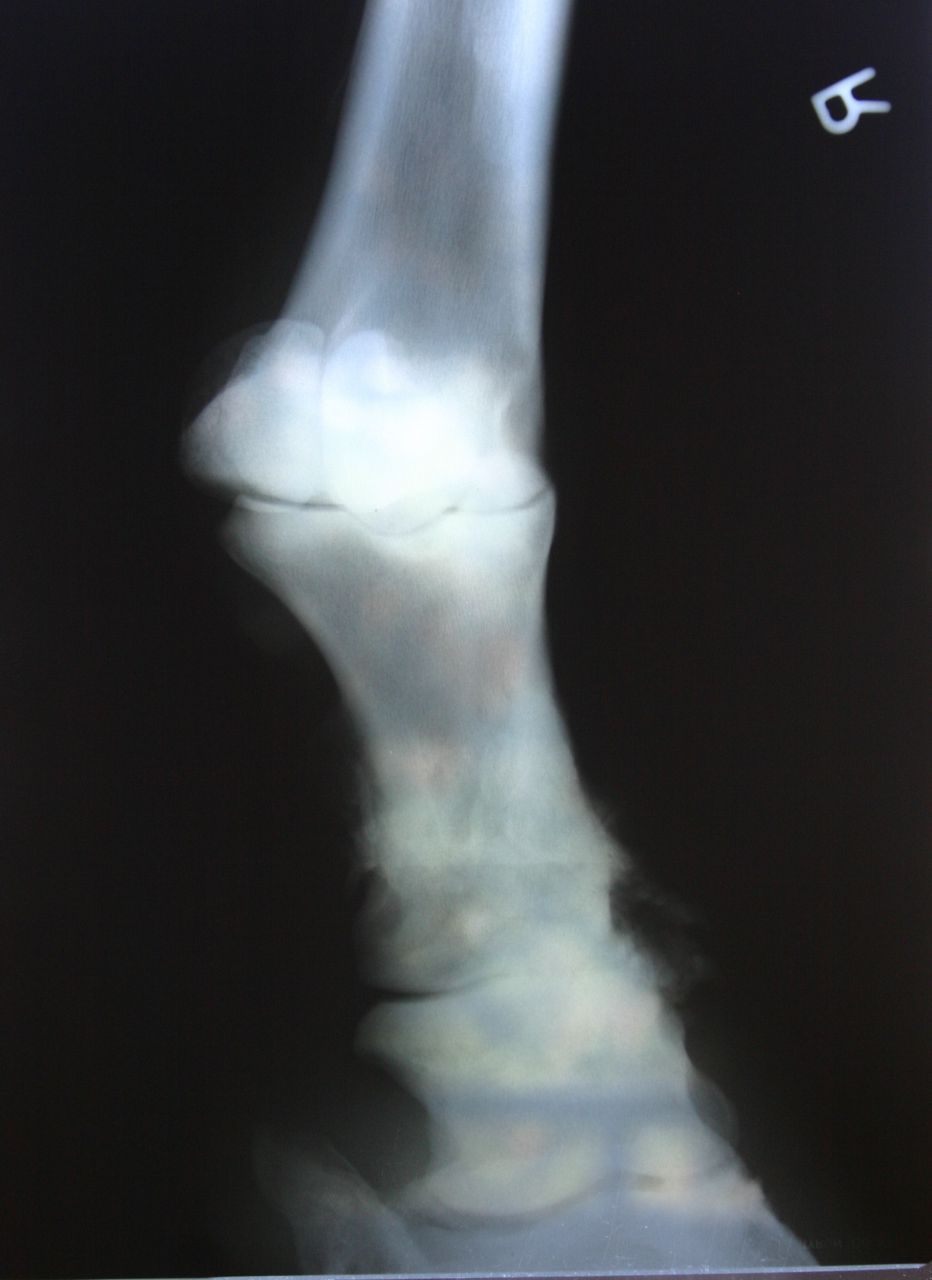

| Dire merci | pour le moment bien, mais ça fait pas longtemps qu'il est sous equipalazone en continu! et puis il avait un autre AI avant, qui était sous forme de pâte, mais j'arrive plus à me rappeler le nom, il me semble que ça finissait par "ure" j'ai fait des photos des dernières radios,s'il y en a que ça intéresse ![]() d'abord l'antérieur droit, le plus touché : on voit bien les formes aux paturons et l'articulation qui est presque entièrement soudée ![]() ![]() ![]() et puis le gauche, un peu moins grave mais bien touché quand même! ![]() ![]() |